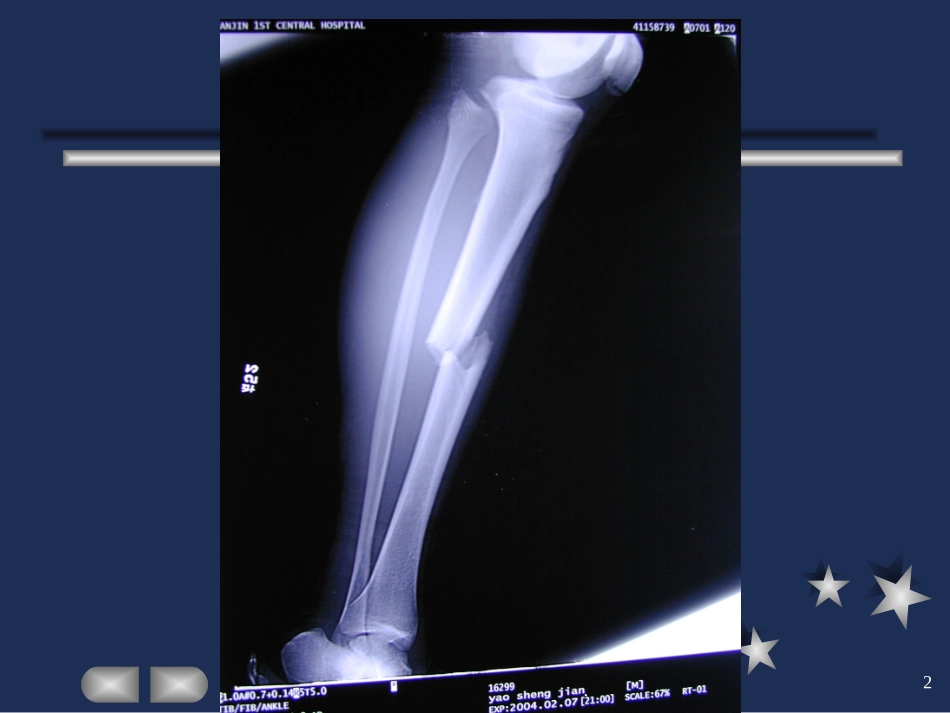

确认删除?

VIP

微信客服